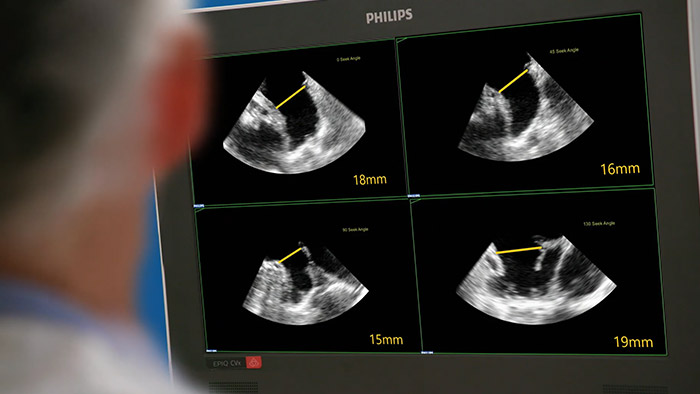

Assessing the left atrial appendage quickly, easily, intuitively. The Philips LAA solution on EPIQ CVxi.

EchoNavigator reorients and combines ultrasound and X-ray information into a single augmented visualisation for guidance and device-tissue relationship assessment. In LAA occlusion EchoNavigator enables the following to elevate confidence and boost efficiency: